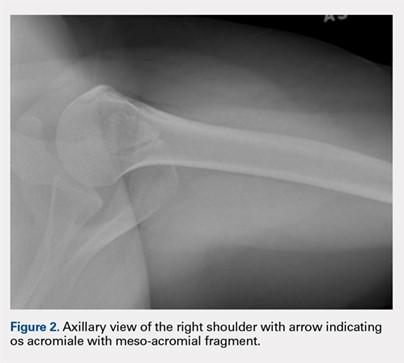

Plain radiographs are usually adequate for diagnosis. Axillary views are most sensitive for detection, which can be difficult to see on anteroposterior radiographs.4 In os acromiale, the unfused segment is connected to the acromioclavicular joint and the coracoid, which can lead to motion of the segment and impingement of the rotator cuff.2-4 Patients frequently experience localized tenderness and symptomatic pain with signs and symptoms of impingement. Rotator cuff tears may occur secondary to chronic impingement.5

The patient is a 19-year-old right-hand-dominant woman who injured her right shoulder while diving into the bleachers during a volleyball game 4 years prior to presentation. She suffered a direct blow to her shoulder and immediately became symptomatic. She underwent a long period of nonoperative management, which included physical therapy, strengthening, nonsteroidal anti-inflammatory drug (NSAID) therapy, and narcotic pain medications. Her primary complaints upon presentation were pain with lifting, as well as mechanical symptoms. On examination, the patient had moderate tenderness directly over the acromion. She also had evidence of mild impingement symptoms. Plain radiographs revealed a mesoacromial-type os acromiale clearly seen on the axillary lateral film (Figure 2). She underwent magnetic resonance imaging, which suggested rotator cuff tendinosis and evidence of edema at the os acromiale site. She underwent a diagnostic injection directly into the site of maximal tenderness at the os, which provided complete transient relief of her pain. Despite the transient pain relief, the patient continued to be symptomatic after the local anesthetic effect wore off. Surgical options were then discussed with the patient.